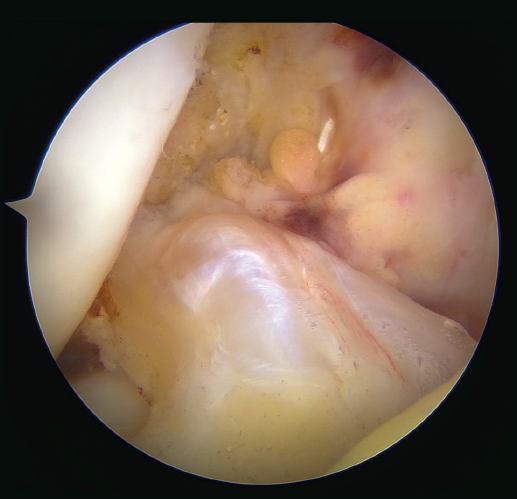

The next step consists of introducing the necessary instruments through the anteromedial portal to make several perforations approximately 1 mm deep in the femoral insertional footprint, with the aforementioned aim of obtaining a bleeding bed to facilitate healing of the ACL. Such drilling can be done manually (with micro- or nanofracture punches) or motorized (PowerPick®, Arthrex), and this step is usually made easier by flexing the knee at about 100°.

Once the bone marrow is stimulated, a short silicone cannula (PassPort®) is placed in the anteromedial portal with the help of vascular forceps. This cannula will help us to organize the suture threads and will make it difficult for Hoffa's fat pad and other soft tissues to get in the way. With the same aim of facilitating suture management (and drilling of the femoral tunnel), an accessory medial portal is now added, in a position medial to the anteromedial portal.

The femoral tunnel is made from this accessory medial portal using a 4.5 mm diameter spear point drill, from the most anterior portion of the insertional footprint of the ACL through the lateral cortex of the femur. Once the tunnel has been completed, the same drill is used to leave a retriever thread through the femoral tunnel, as it is equipped with an eyelet. It is important to secure the two ends of this thread together outside of the knee in order to avoid losing either of them during surgery.